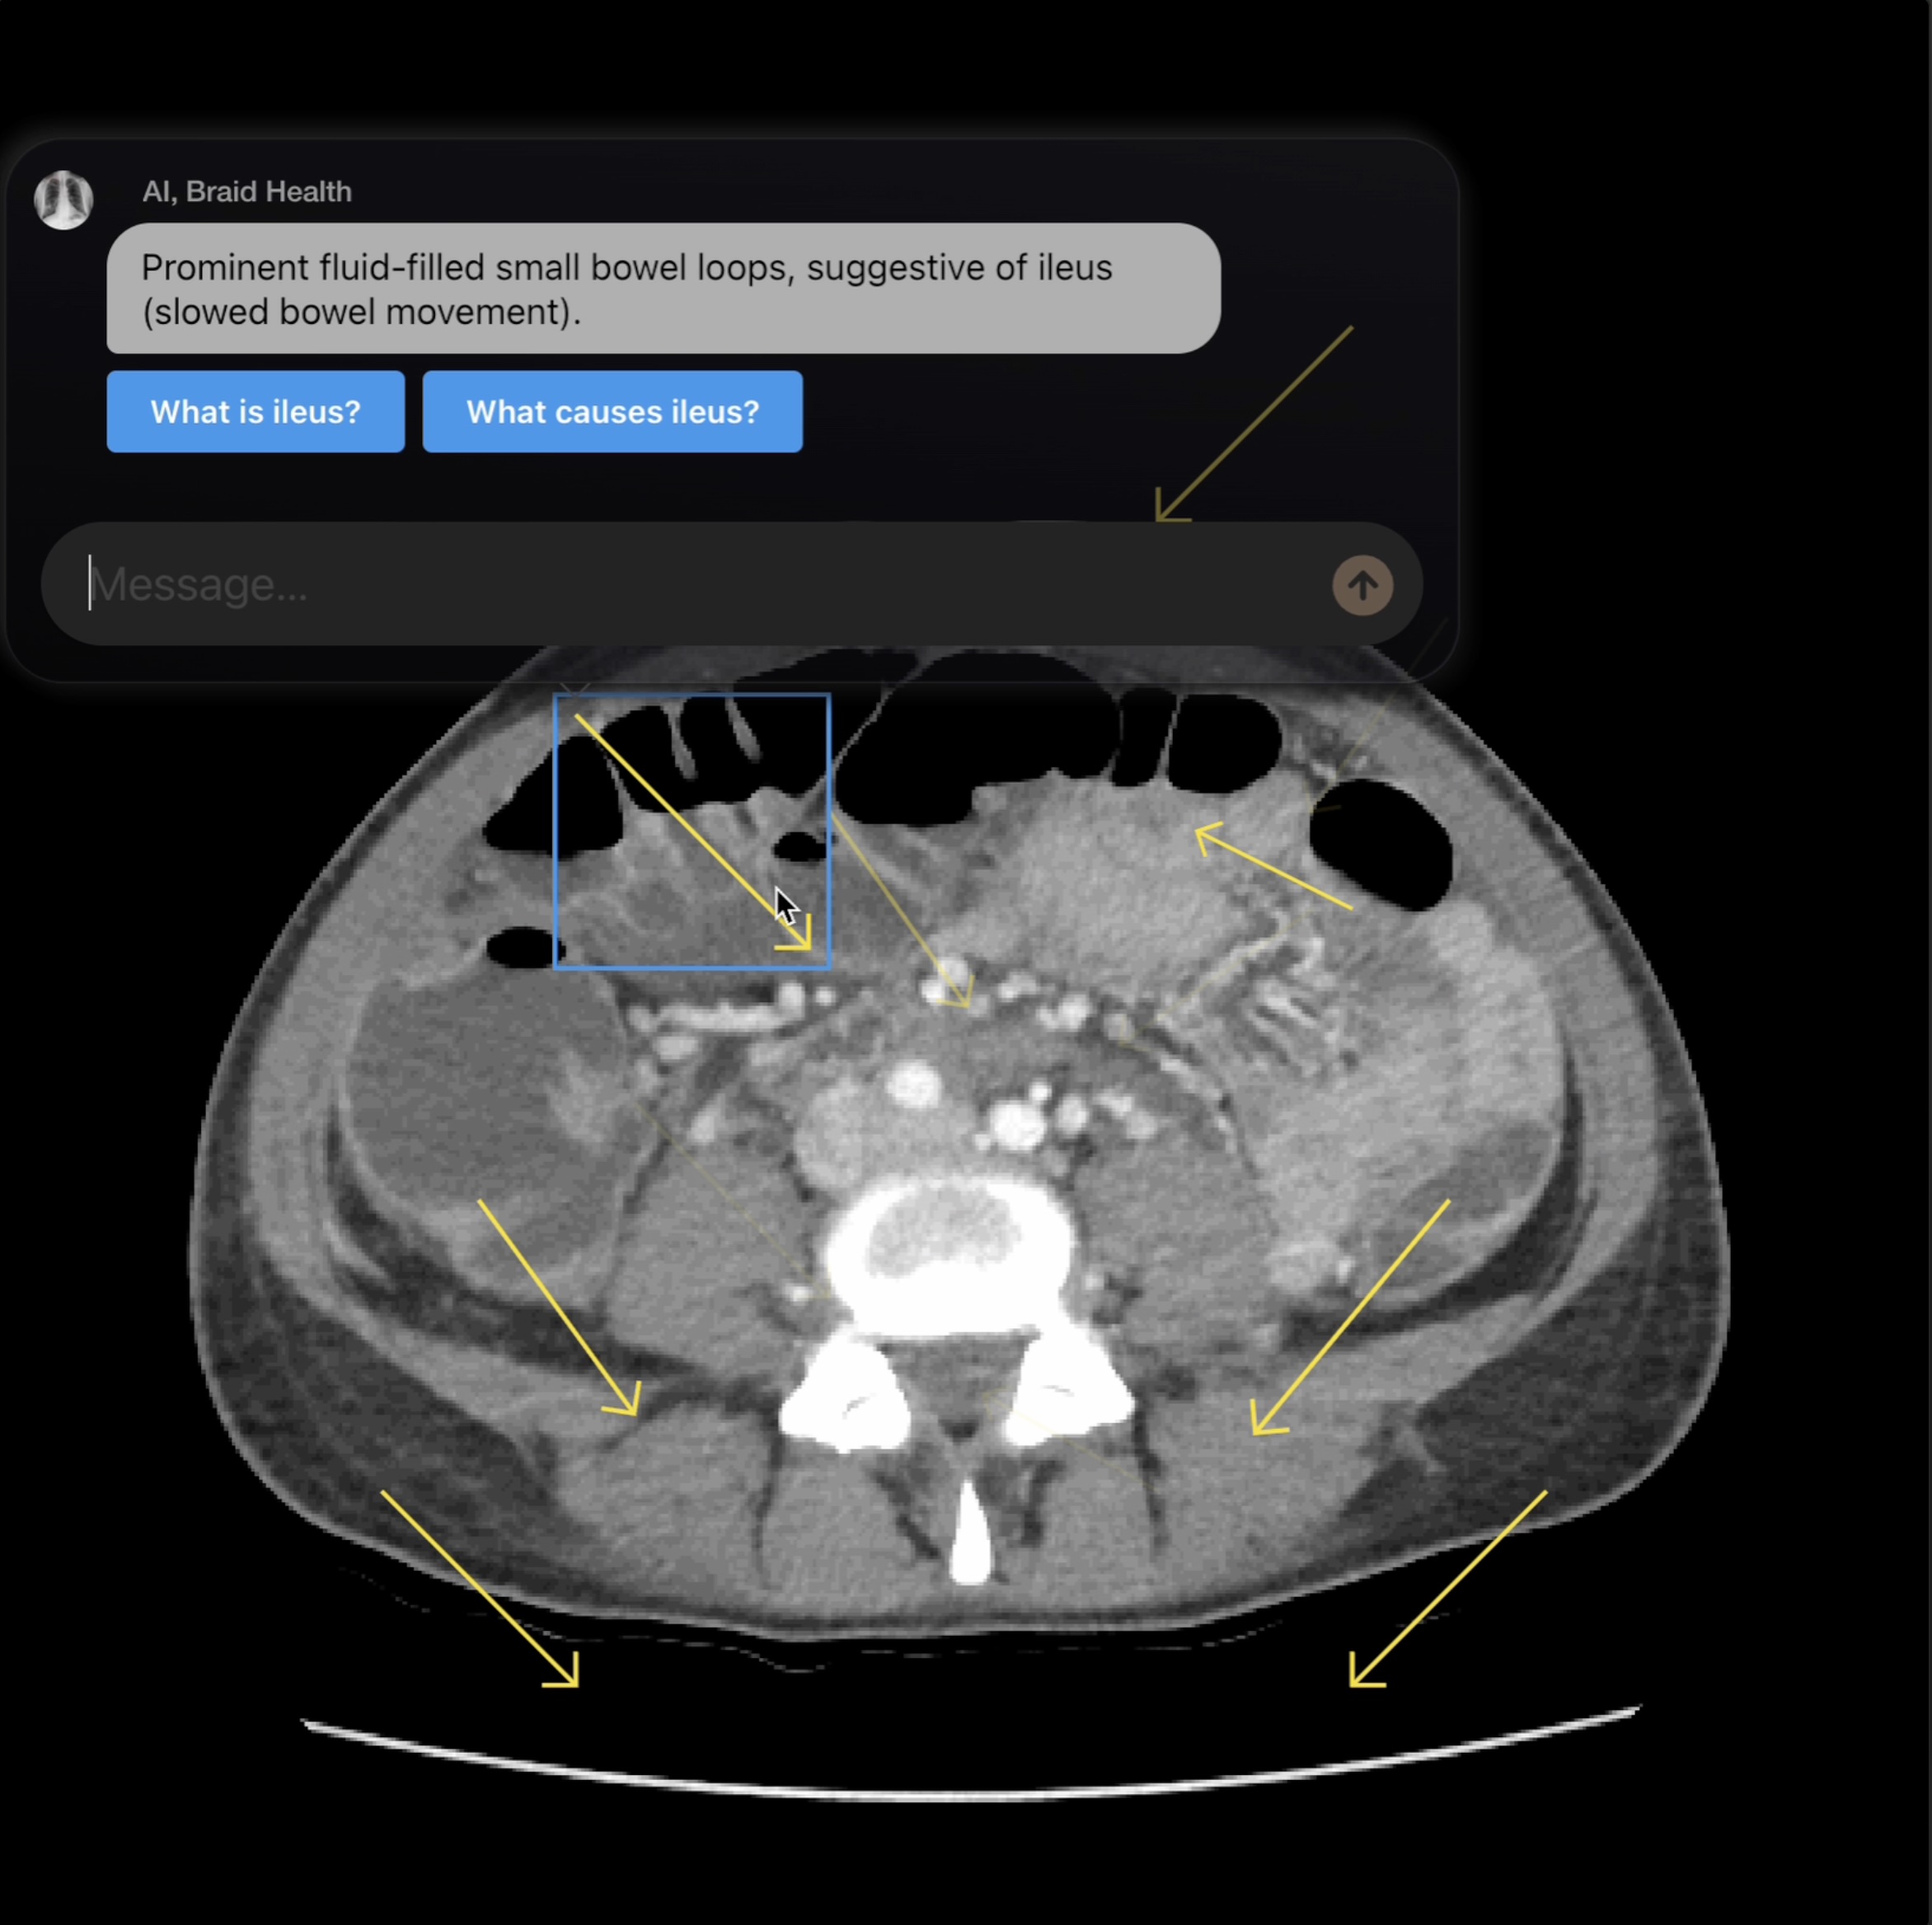

- Capabilities of Modern AI: Discover various applications, from healthcare to finance, that enhance efficiency and decision-making.